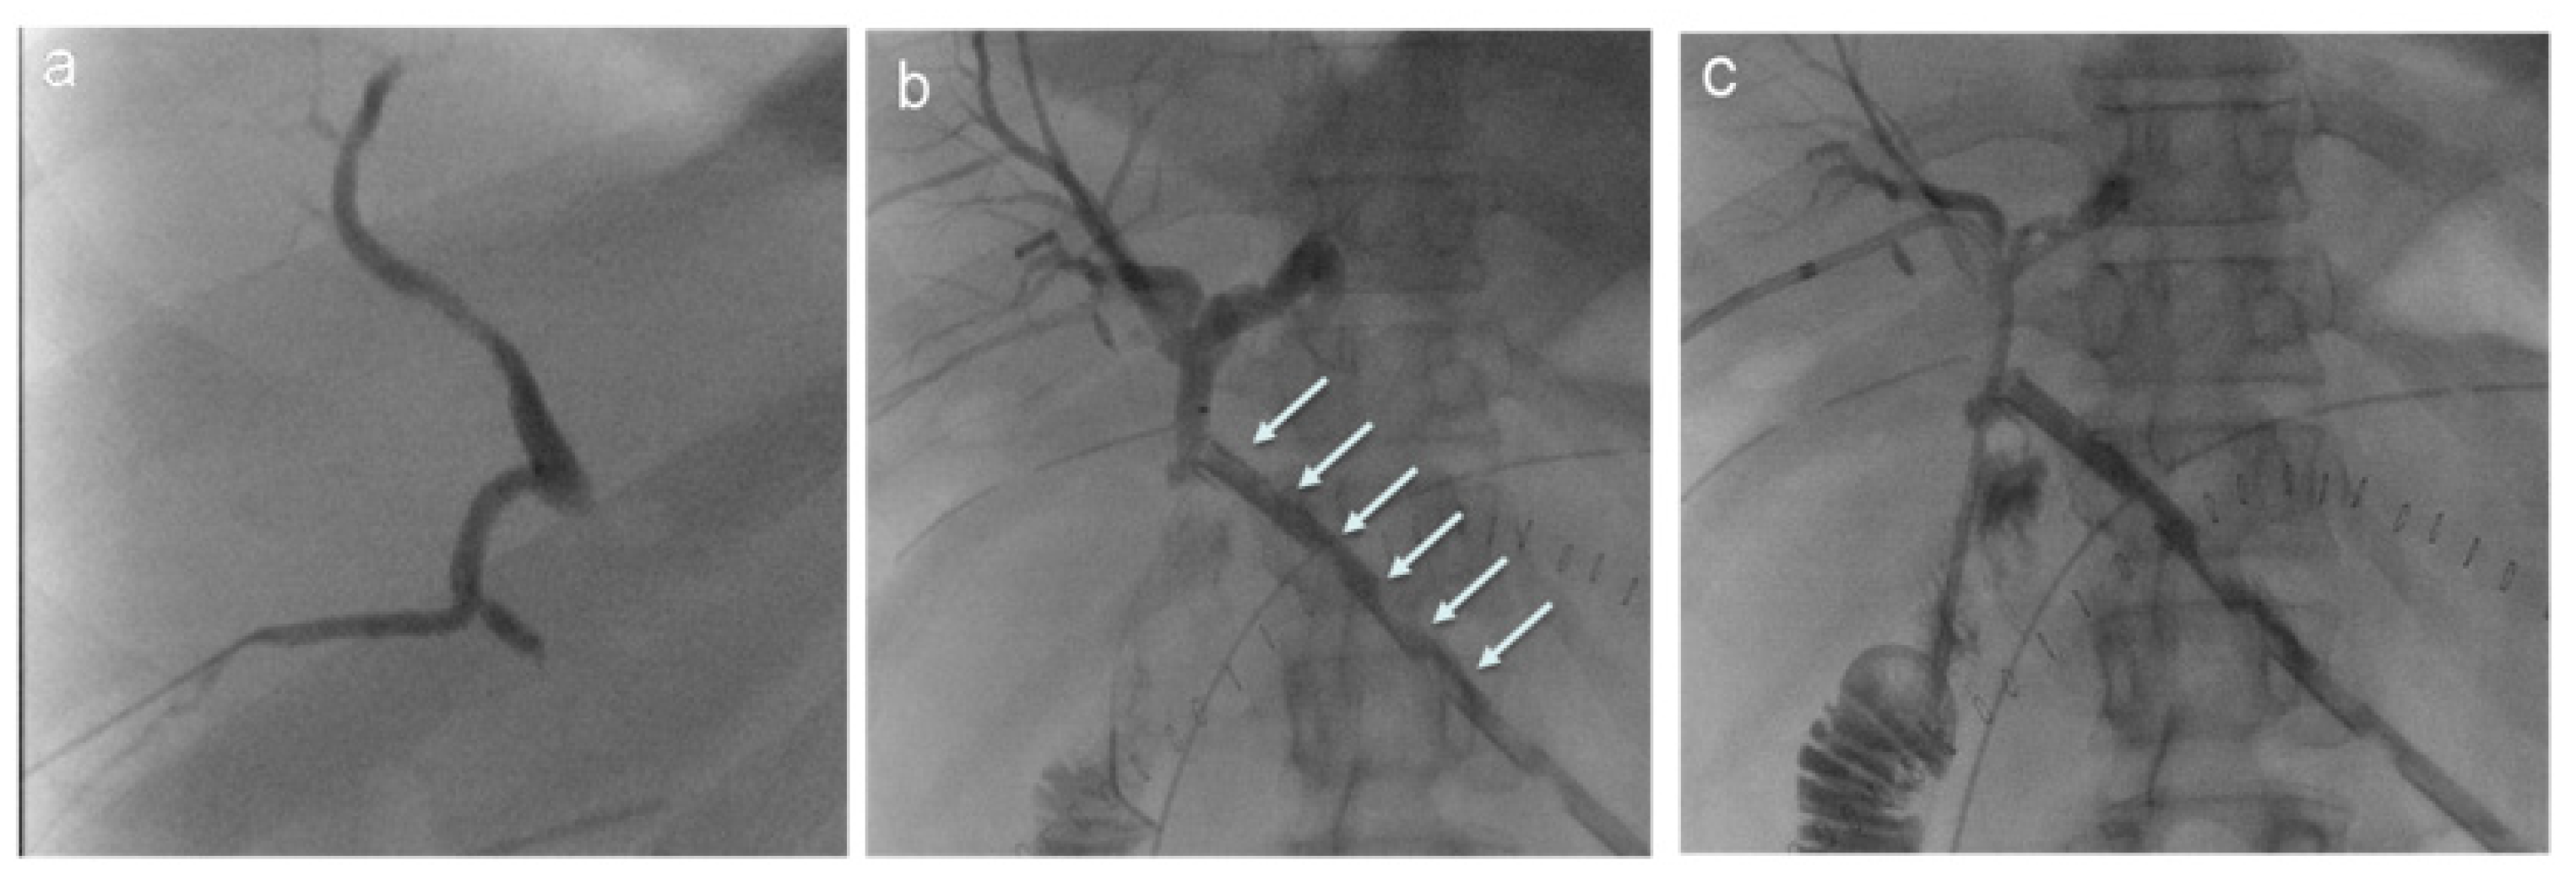

3. Percutaneous Transhepatic Biliary Drainage